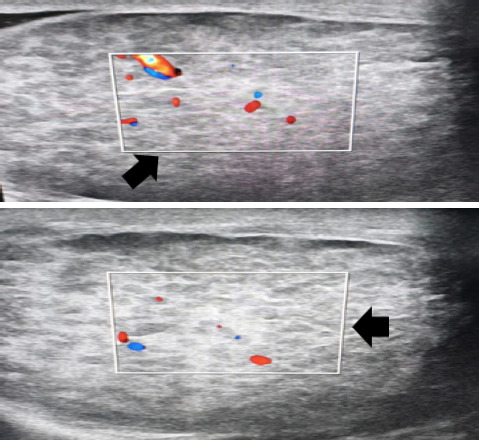

Extrapulmonary tuberculosis constitutes about 20% of all cases of tuberculosis. It involves organs other than the lungs, such as lymph nodes, the genitourinary tract, abdomen, skin, joints and bones, and meninges. Tuberculosis of the testis is a rare disease. The diagnosis of testicular tuberculosis could be confused with testicular cancer, sarcoidosis or metastases. Herein, we describe the ultrasonography of five patients with testicular tuberculosis. This case series highlights the importance of ultrasonography in the diagnosis of rare form of extra pulmonary tuberculosis.